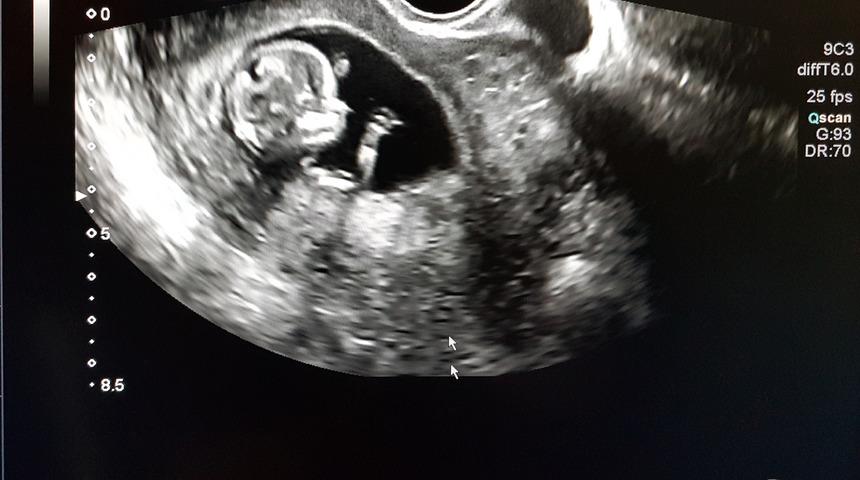

Slovakya, kürtaj olmayı düşünen kadınların operasyondan önce ultrason görüntülerini izlemesini hatta fetüsün kalp atışlarını dinlemesini zorunlu kılacak bir yasa tasarısını oylamaya sundu. Tasarı büyük tepki çekti.

Parlamentoda oylamaya sunulan tasarıya göre, kürtaj yaptırmayı düşünen kadınlar, ultrason görüntülerini görmeye zorlanacak. Bununla da kalmayan tasarı, ayrıca fetüsün kalp atışlarının dinletilmesini de zorunlu kılıyor.